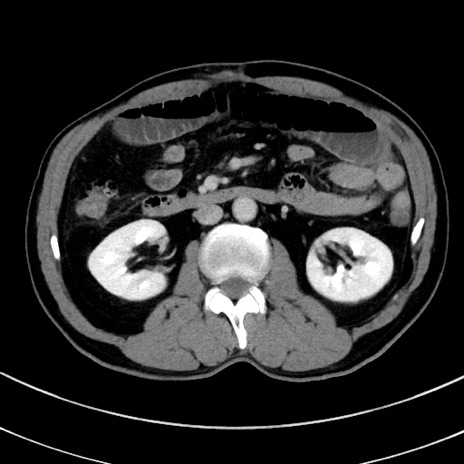

冠状断像

【症例】 60歳代男性

【主訴】 黒色吐物

【現病歴】 4日前から嘔気自覚、2日前の朝食後にも嘔気あり、自分で手で嘔吐反射起こし嘔吐したところ血が混ざっていたため受診。

【既往歴】 5年前汎発性腹膜炎を伴う急性虫垂炎で手術、高血圧、前立腺肥大症、高脂血症

【身体所見】 腹部正中に手術癩痕あり 腹部平坦・軟圧痛なし膨満感あり

【データ】WBC 8400、CRP 4.54